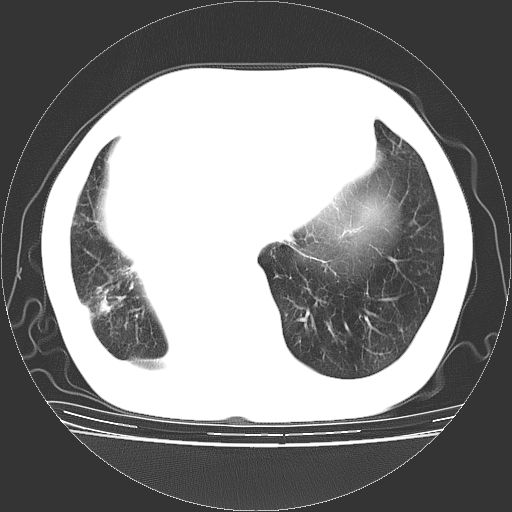

女,70岁,咳嗽、咳痰一个月,低热一周。

1.左上肺结核,部分纤维化。右肺中下叶部分肺不张,内见液化、坏死及点状钙化,右中下叶支气管壁增厚、管腔狭窄,见多个点状钙化,结合临床考虑支气管内膜结核,建议痰检查抗酸杆菌并参考血沉。两肺多个小圆点状高密度灶,境界模糊,多考虑结核肺内播散。但本人年龄较大首先应支气管镜检以除外右肺癌。

支持,首先一元论解释。胸主动脉部分层面环形低密度,中心强化。环形影不强化。不象真假腔的改变。我考虑动脉炎,不太支持夹层动脉瘤-和大家的观点不一致,希望楼主让患者再做个心血管的彩超吧。